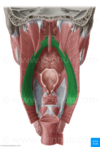

What is this muscle

The Rhomboid minor